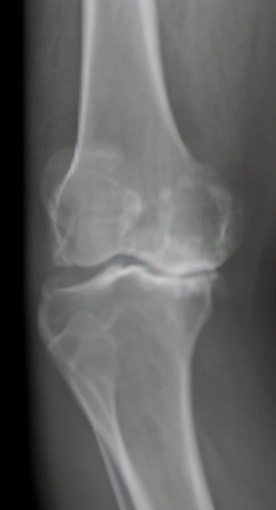

图1 膝骨关节炎x片表现:c晚期

膝骨关节炎的早期表现为膝关节疼痛,随着病情进展,会出现疼痛加重并活动受限,关节畸形。患了膝骨关节炎该如何治疗?首先需明确, 治疗的目的主要是2个,即解决疼痛,改善关节功能。 解决了这两个问题,最终就会实现生活质量的提高。那么如何缓解疼痛?怎样改善功能?这是每个膝骨关节炎患者最关心的问题,这需要根据病情的严重程度,采取个体化的治疗手段。患者希望以最小的代价获得最满意的疗效,这也是医生不竭的医术追求。

重建治疗亦即关节置换治疗,这一阶段所采取的手术方式相对来说是较大的手术了,退变磨损的关节面难以通过自身的修复或局部处理使病情逆转,只能接受表面置换。膝关节表面置换包括部分表面置换术(单髁置换)和全膝关节表面置换术(全膝置换)。通俗来讲,单髁置换主要是解决膝关节内侧或外侧磨损(疼痛)问题,而全膝关节置换是解决全膝关节磨损(疼痛)问题。 重建治疗的手术,是针对骨关节炎的晚期阶段,是终极治疗方式。当然,如果不得不选择这一治疗方式,也大可不必害怕,人工关节置换已经是非常成熟的手术,关节置换术可以有效缓解疼痛、改善功能,使你的膝关节焕发新生,重启人生精彩。